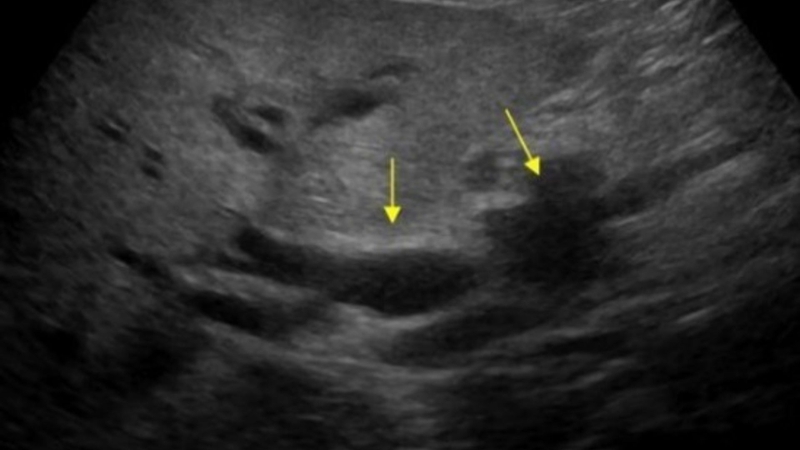

U bóng Vater là khối u xuất phát từ vùng bóng Vater, nơi ống mật chủ và ống tụy đổ vào tá tràng. Đây là vị trí trọng yếu trong hệ tiêu hóa, giúp điều tiết dịch mật và enzyme tiêu hóa.